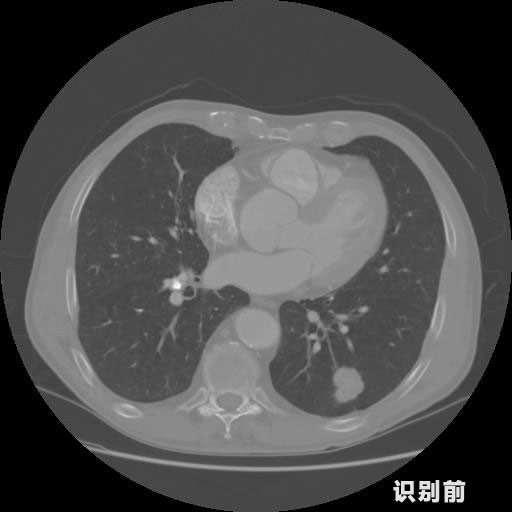

英特健康A(chǔ)I深度學習醫(yī)療圖像識別系統(tǒng)案例_胸部CT

1.發(fā)現(xiàn)肺結(jié)節(jié)的可能性為95.56%---位于框指數(shù)位置:[331.70554 366.13406 365.21707 403.96234]